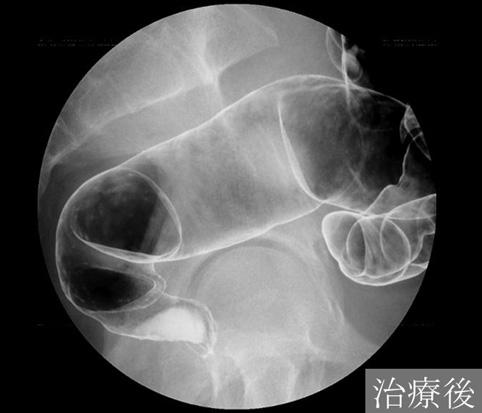

A case of amebiasis which showed the typical morphologic findings corresponding to the amebic colitis.

Inflammatory or ulcerative disease / lesions/Amebiasis

Location

Large intestine(Colon)/Rectum

Technique, Method